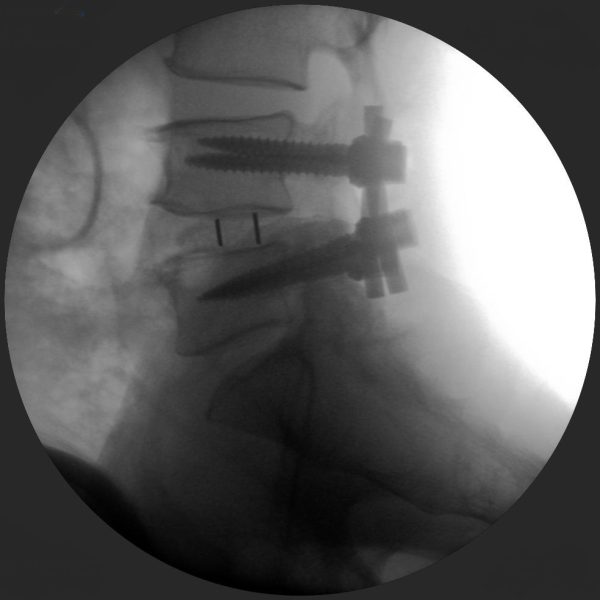

High-quality imaging

Skan-C uses advanced imaging technology, such as pulsed fluoroscopy and digital subtraction angiography, to provide highly detailed images of the affected area. This allows doctors to perform procedures with increased precision and accuracy, and better patient outcome

Clinical Evidence

Skan-C is a great C-arm for neurology treatments for several reasons